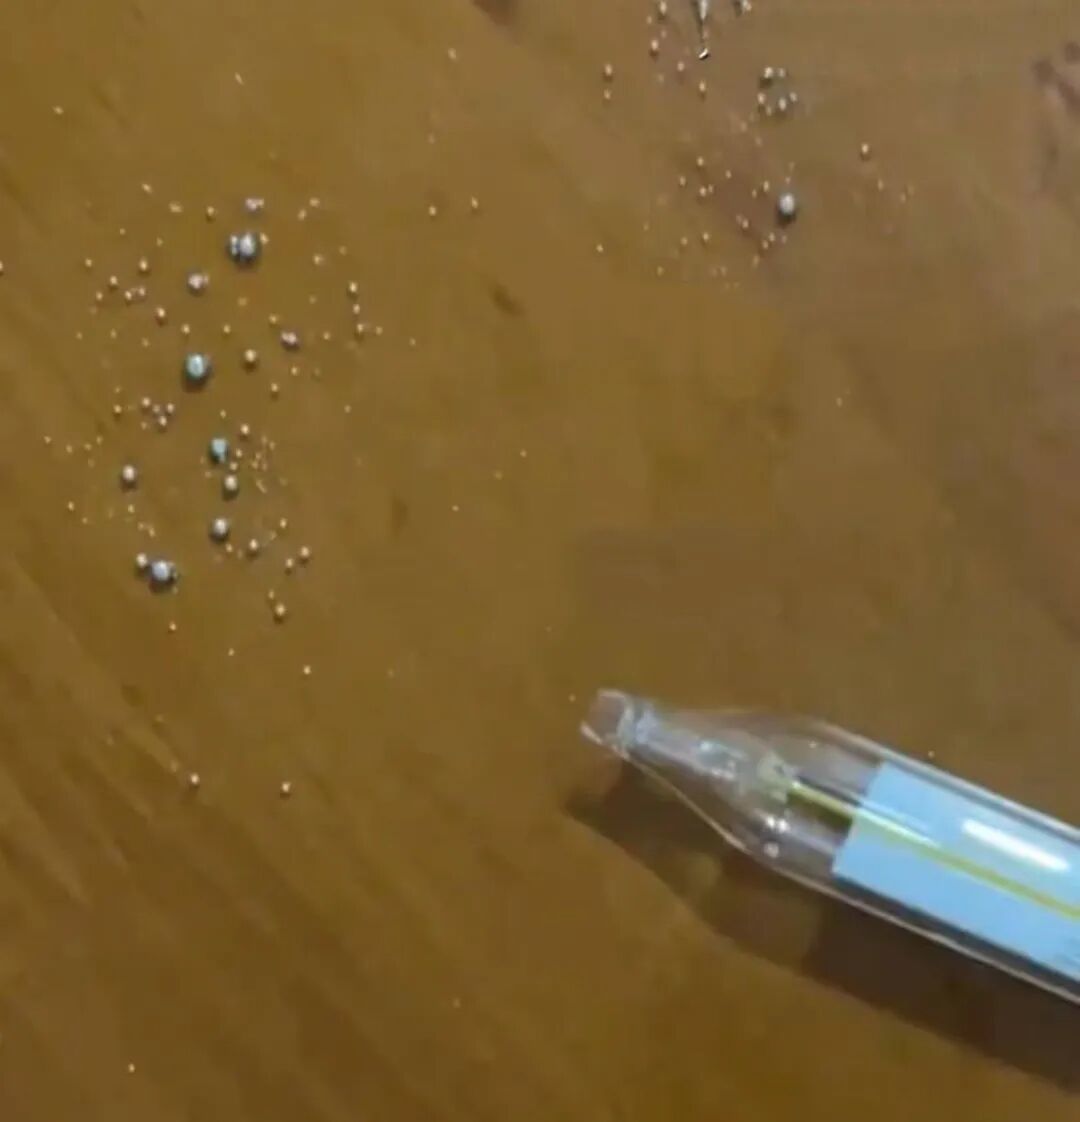

CT检查发现蛛网膜下腔出血,脑内血肿;进一步接受脑血管造影(CTA)检查,明确左侧大脑中动脉存在动脉瘤,瘤体破裂引发脑出血。 “从影像上看,动脉瘤已经破裂,整个脑子里弥漫着血。”陈飞宇记得,血管直径不过2mm,动脉瘤最长径却有4mm,在血流冲击下,破裂动脉瘤的破口就像肥皂泡一样脆弱易碎。出血导致颅内压持续升高,如果不尽快手术,可能会对脑组织、神经造成严重损伤。陈飞宇团队当机立断,精准判断病灶并行血管内介入治疗,经1个小时的手术,这枚埋藏在赵女士颅内的“定时炸弹”终于被成功扫除。

手术前后影像对比。